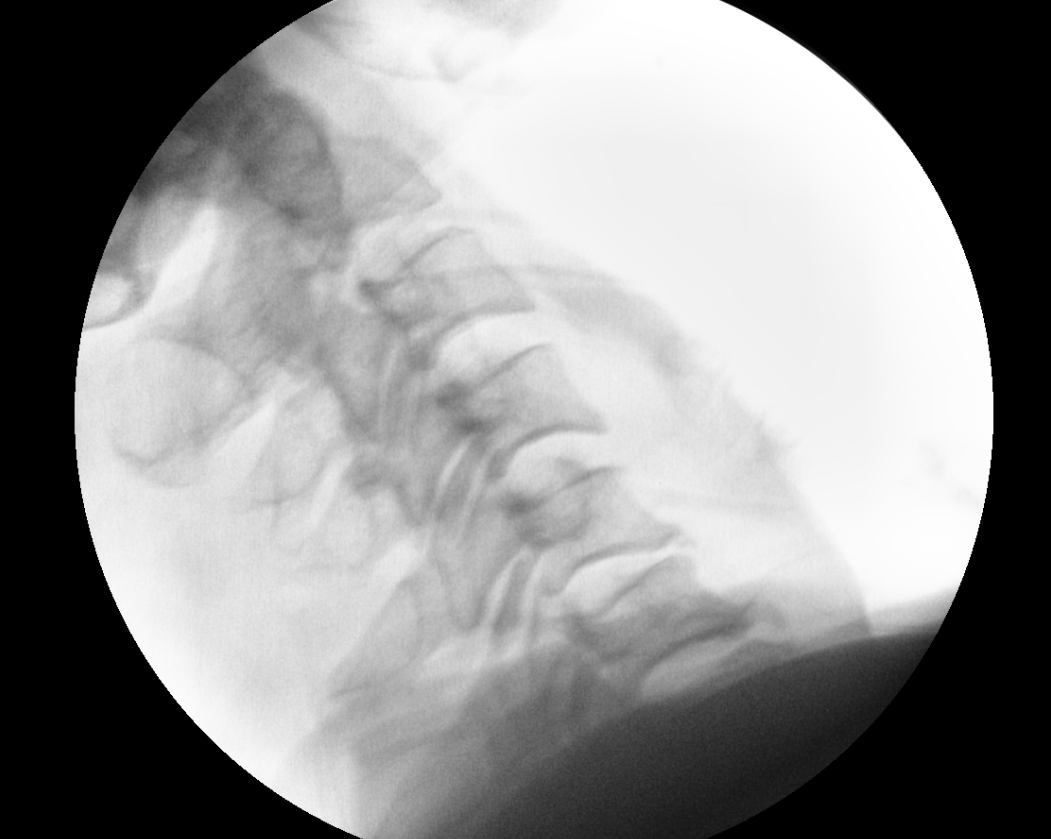

x ray 측면에서 보면 경추 5/6 후관절 탈골이 확인이 됨.

reduction 된 것을 확인 하였음.